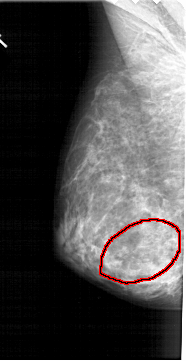

A_1379_1.LEFT_CC

LEFT_CC LINES 5086 PIXELS_PER_LINE 2596 BITS_PER_PIXEL 12 RESOLUTION 43.5 OVERLAY

FILE: A_1379_1.LEFT_CC.OVERLAY

TOTAL_ABNORMALITIES 1

ABNORMALITY 1

LESION_TYPE MASS SHAPE IRREGULAR MARGINS ILL_DEFINED

ASSESSMENT 4

SUBTLETY 4

PATHOLOGY BENIGN

TOTAL_OUTLINES 1